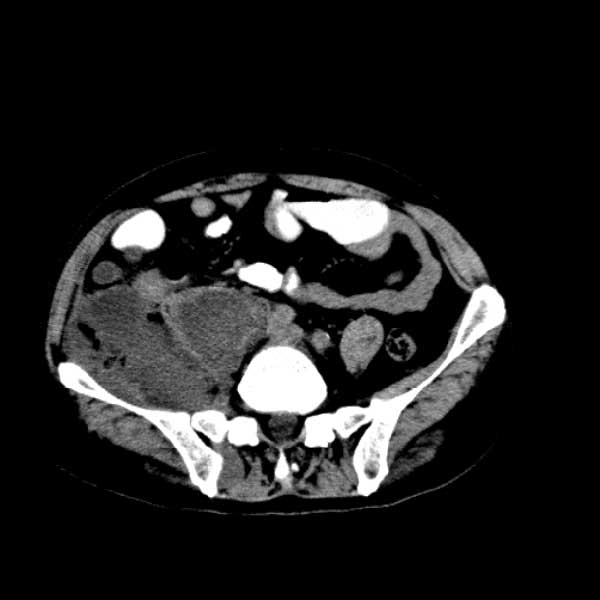

标题: CT13513:男 71 腹部疼痛20余天,近几天高热就诊,骨窗未见异 [打印本页]

考虑右侧腰大肌脓肿,向右髂窝、右腹股沟流注。

支持化脓性阑尾炎伴右髂窝脓肿、腰大肌腰方肌脓肿形成。

考虑腹腔及盆腔化脓性炎症,累及右侧髋关节及腹股沟区.

首先考虑化脓性阑尾炎伴腰大肌、腰方肌脓肿,不除外回盲部结核。

回盲部癌待排除。

患者肠镜检查考虑结肠癌,病理证实

患者肠镜检查考虑结肠癌,病理证实。肺部ct可见多发结节,考虑转移